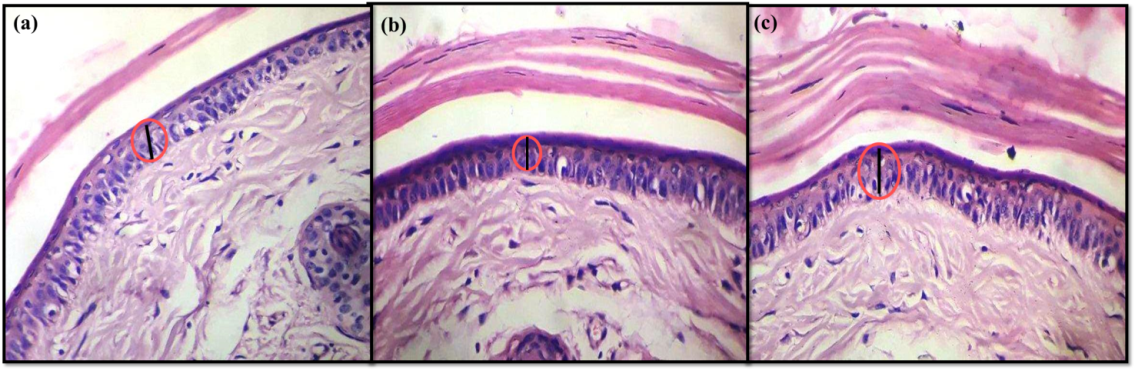

Histopathology

Histopathological observations of the longitudinal sections of mouse tail skin from placebo Group III revealed the normal thickness of the epidermis, presence of ridges and presence of parakeratotic layer [fig. 12 (c)]. The mouse tail skin from standard Group I (Clobetasol propionate cream 0.05%) and test Group II (NLCs) groups revealed marked reduction in the thickness of the epidermal layer, a decrease in ridges and presence of granular cells in orthokeratotic layer [fig. 12 (a) and (b)] respectively.

Fig. 12: Histopathology of mice tail skin for, a) Standard Group I, b) Test group II, c) Placebo group III